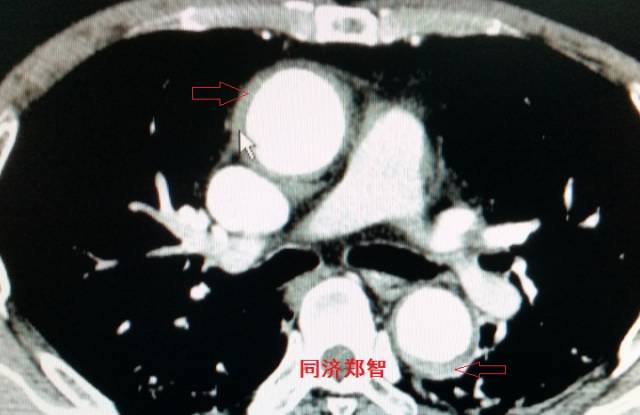

胸部平扫CT提示升主动脉增宽(红色星形标记),CTA证实A型主动脉夹层伴升主动脉夹层动脉瘤形成。

病例三

胸部平扫CT提示胸降动脉增宽(红色星形标记),CTA证实B型主动脉夹层伴降主动脉夹层动脉瘤形成。